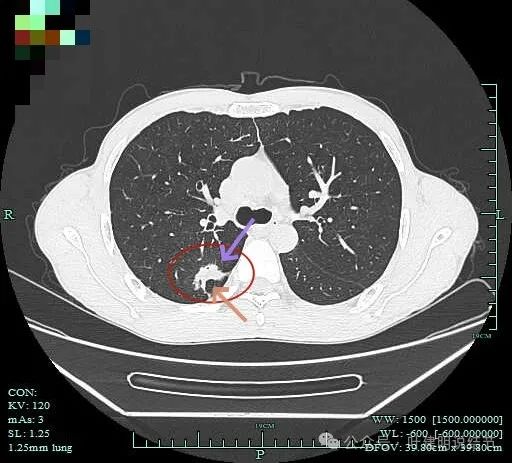

病灶2:

病灶出现,密度杂乱。

有磨玻璃成分,且轮廓清,磨玻璃边缘有细毛刺征,实性成分的边缘毛糙不平,形态不规则。

灶内有僵硬支气管走行,边上少许磨玻璃成分,病灶有一定收缩力。

灶内支气管穿行且显得僵硬。

胸膜牵拉,灶内支气管通气征并显僵硬,部分边缘有毛刺征。

有血管进入并异常增粗;病灶有分叶征,有毛刺征,也有胸膜牵拉征。

病灶有细毛刺征,感觉有收缩力。

实性成分为主,边上少许磨玻璃成分。

叶间胸膜牵拉。

这个病灶是非常典型的恶性的,总体上基本上是实性成分,但边上仍有少许磨玻璃,而磨玻璃成分有分叶与细毛刺,病灶内部有支气管通气征,且支气管显僵硬,又有异常增粗的血管进入。再加上胸膜牵拉、叶间裂牵拉,整体轮廓较清,周围肺野清爽,没有卫星灶。所以基本上就是浸润性癌了的。